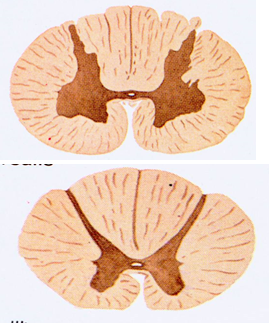

脊髓由灰质和白质两大部分组成。在脊髓的横切面上,可见中央有一细小的中央管,围绕中央管周围是“H”形的灰质,灰质的外周是白质。

每侧的灰质,前部扩大为前角或前柱;后部狭细为后角或后柱,它由后向前又可分为头、颈和基底三部分;在胸髓和上部腰髓(L1~L3),前、后角之间有向外伸出的侧角或侧柱;前、后角之间的区域为中间带;中央管前、后的灰质分别称为灰质前连合和灰质后连合,连接两侧的灰质。因灰质前、后连合位于中央管周围,又称中央灰质。

白质借脊髓的纵沟分为3个索,前正中裂与前外侧沟之间为前索;前、后外侧沟之间为外侧索;后外侧沟与后正中沟之间为后索。在灰质前连合的前方有纤维横越,称白质前连合。在后角基部外侧与白质之间,灰、白质混合交织,称网状结构,在颈部比较明显。